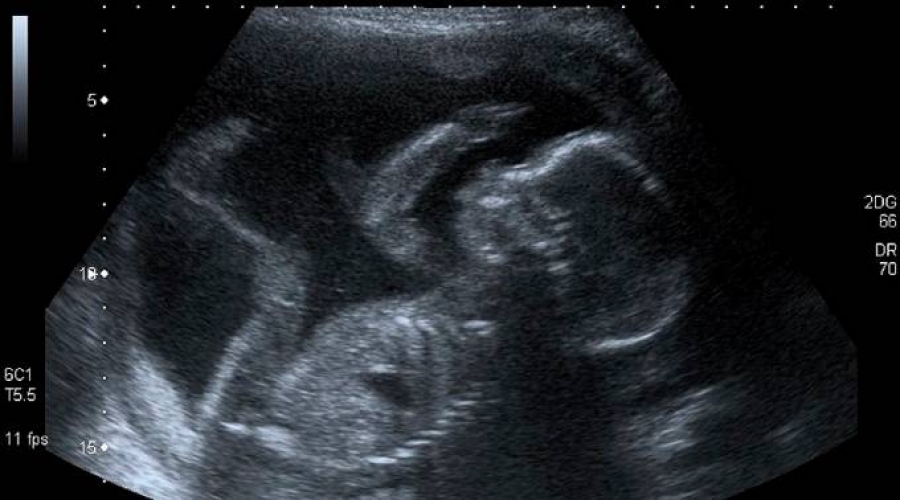

Los obispos de Bolivia manifestaron su preocupación por «el avance de la cultura de la muerte y el descarte» que podría traer consigo la reforma del Código Penal, que busca abrir la posibilidad del aborto hasta las 8 semanas de embarazo para las mujeres pobres y estudiantes.